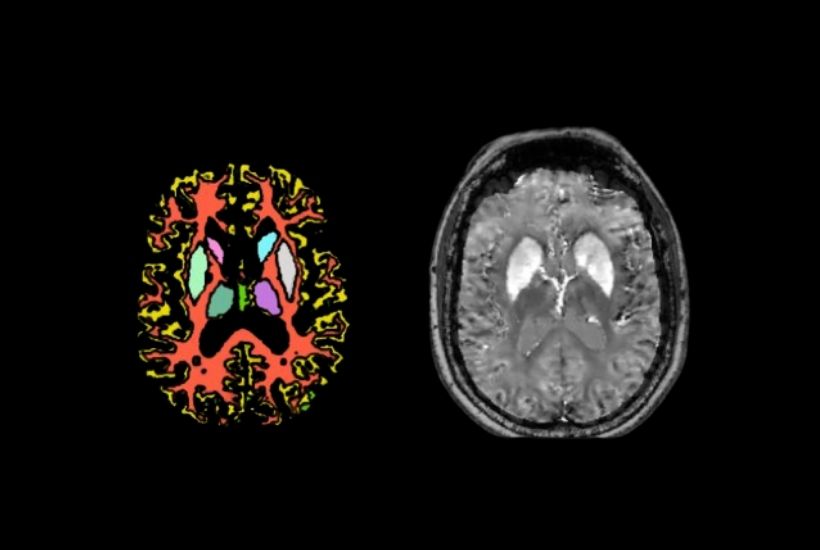

CEA NEUROSPIN x GHU SAINTE-ANNE

QSM4 ALZHEIMER DISEASE

Objectifs

Diagnostiquer plus tôt, mieux stratifier les patients :

- Comparer les images cérébrales des malades avec les images cérébrales du vieillissement cognitif normal

- Établir des corrélations entre l’imagerie du fer et les manifestations cliniques de la maladie

- Caractériser les profils atypiques de la maladie d’Alzheimer grâce aux informations fournies par l’imagerie du fer.